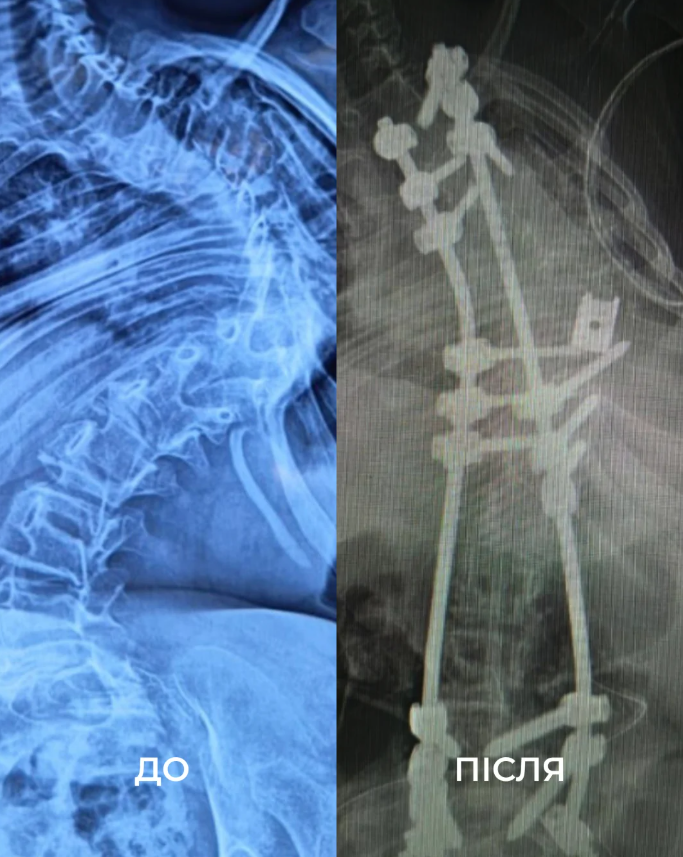

У ребенка диагностировали сколиоз IV степени, вызванный редким заболеванием – миопатией Бетлема. С годами ее состояние ухудшалось – позвоночник ребенка искривился на 160 градусов, она испытывала постоянную боль и передвигалась только с помощью ходунков или в инвалидном кресле.

"Чтобы исправить ее сколиоз, нам нужно было удалить целый позвонок. В первый день операции мы закрепили ее позвоночник винтами. А затем уже на второй день удалили несколько ребер, изолировали спинной мозг и установили титановую клетку", – рассказал Диржка.

В итоге девочка провела 18 часов под наркозом. Хирургам удалось выровнять позвоночник девочки на 85%.

"Спина действительно изменилась. Больше нет того горба из ребер. Она вытянулась, стала выше. Мы удивлены! И врачи сами сказали, что сделали больше, чем ожидали", – отметила мама пациентки.